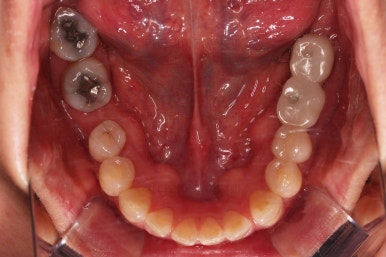

초진 시 입안의 모습입니다.

아랫니 큰 어금니 하나가 없어서 임플란트를 원하셨던 환자분이셨어요.

앞니가 조금 삐뚤고, 아랫니는 사이사이에 틈새가 있었지만 전체적인 교정은 원치 않으셨어요.